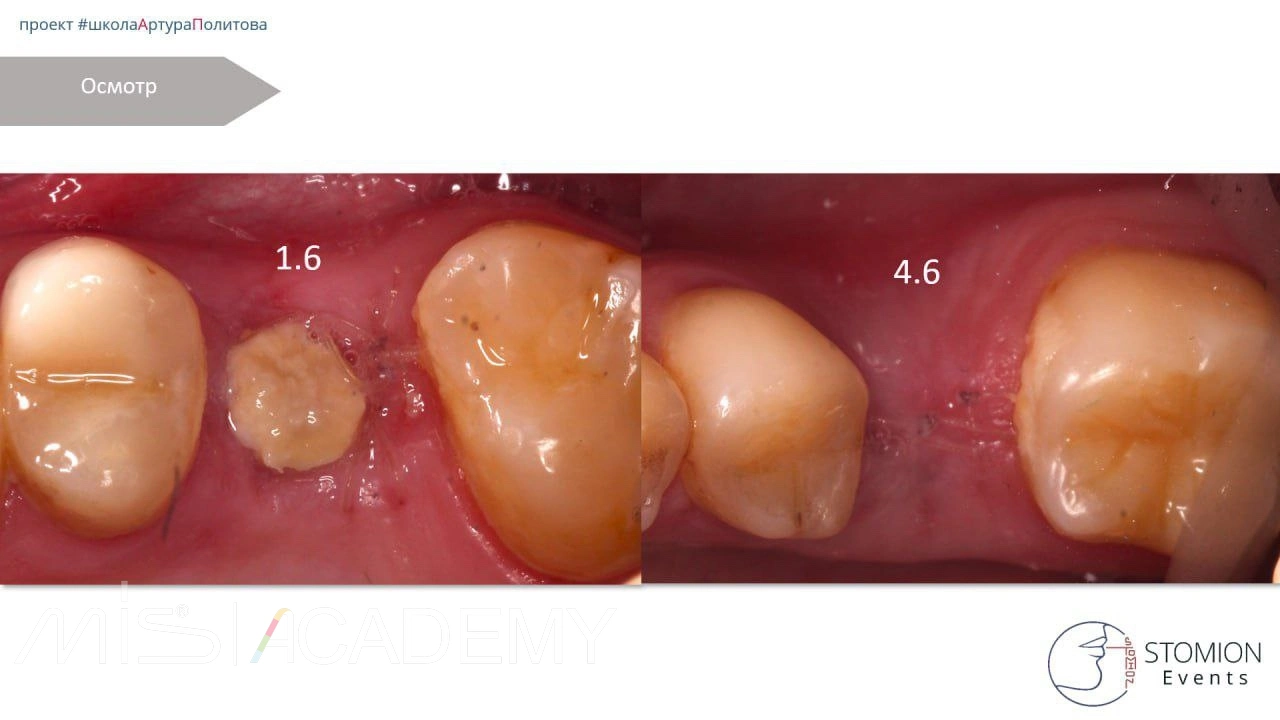

— Протезирование с платформы имплантата.

— 4.6 — винтовая фиксация, 1.6 — цементная.